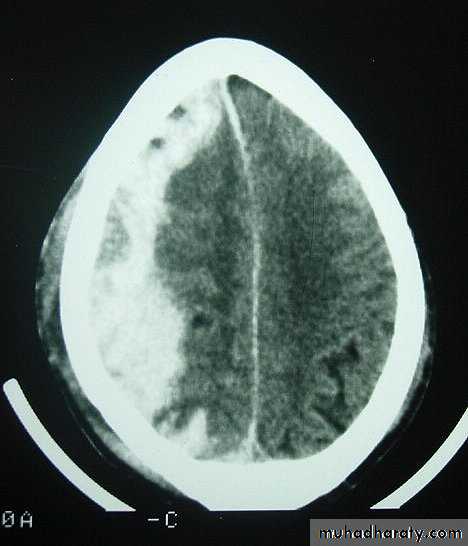

Acute Subdural Haematoma

Clinical Picture: patient will present with a picture similar to that of an extradural haematoma, but there is persistent loss of consciousness with no lucid interval.

Ct scan will show a concave hyperdence collection because blood follows the subdural space over the convexity of the brain.

Acute Subdural Haematoma are rapidly evolving lesions and early evacuation via craniotomy is mandatory.